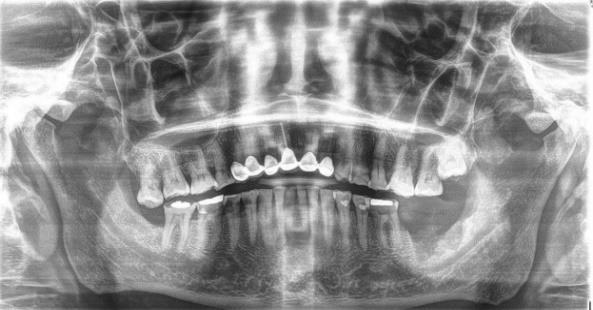

Presentación de caso clínico

Paciente masculino de 63 años de edad, presenta lesión en reborde alveolar

zona de segundo y tercer molar inferior, eritematosa, de forma irregular, de bordes elevados, consistencia blanda que se desprende fácilmente, causa dolor persistente a la manipulación con presencia de sangrado a la palpación y exudado. (Fig.10) de 2 meses de evolución, ha sido tratado con agua oxigenada y tratamientos caseros sin mejoría, con antecedentes de tabaquismo y alcohol. A la exploración radiográfica se aprecia lesión radiolúcida maldelimitada(Fig.11).

Nota:Úlceraquenocicatriza(FotocortesíaDra.JazmínFuentesMarroquín).

Fig 10.

Úlcera que no cicatriza

Fig. 11

Ortopantomografía; lesión radiolúcida mal delimitada localizada en tercer cuadrante, autoría propia.

Nota:FotocortesíaDra.JazmínFuentesMarroquín